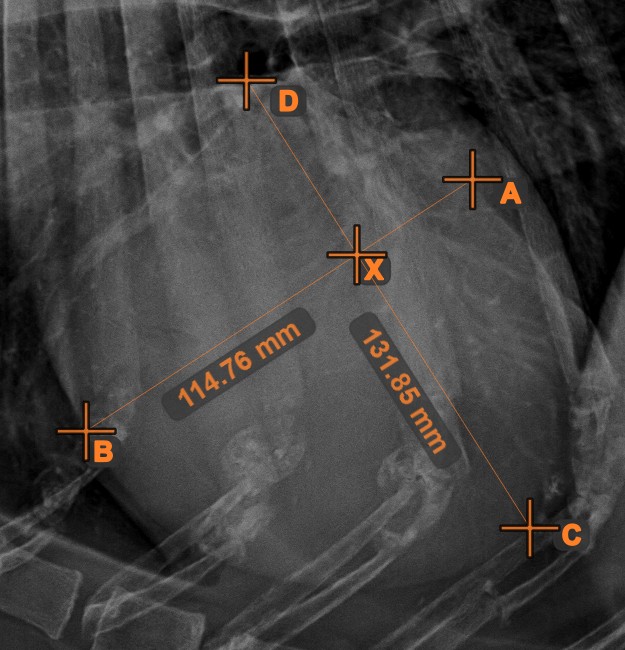

Line Intersection¶

Quickly and accurately locate and mark the intersection point between two existing lines by using the Line Intersection

tool.

Select the tool from the left toolbar and assign it to one of the available mouse buttons. Select two lines that have already been drawn on the scene to complete the measurement. The intersection point of the line will be automatically calculated and marked on the scene. The intersection point of two lines will always be marked with the letter X.

Information

If two lines do not intersect directly, the intersection point of their extended projections on the scene will be marked.